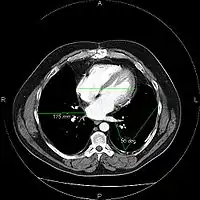

An image as stored on a picture archiving and communication system (PACS)

The same image following contrast adjustment, sharpening and measurement tags added by the system